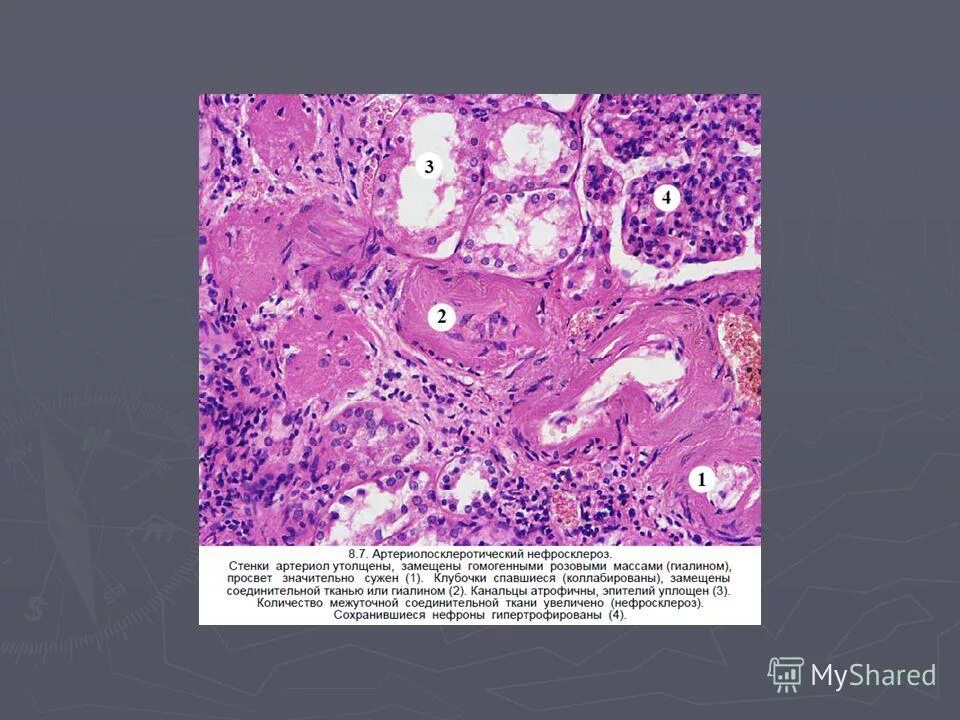

Патологическая анатомия содержание